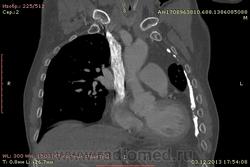

Ребята, вы что, какая жидкость? Чистая известь, посмотрите в костном окне. Отставить натив (в данном случае, хотя для аневризм он обычно нужен). Отставить тромбоз верхней полой вены (потоковые артефакты, не дело вены в артериальную фазу оценивать). Отставить аневризму  аорты, поперчник восходящего отдела на уровне легочного ствола 42мм. А вот легочная гипертензия, здравствуй: поперечник легочного ствола - 37мм, ПЛА - 25мм, ЛЛА - 25мм, НАо - 25-34мм.

намерил аорту, всё таки есть аневризматическое расширение луковицы

на VRT-реконструкции. плотность до + 1000 HU. видел такое как посттуберкулезные обызвествления плевры, надо завтра ещё раз поговорить с лечащим врачом, может ошиблись